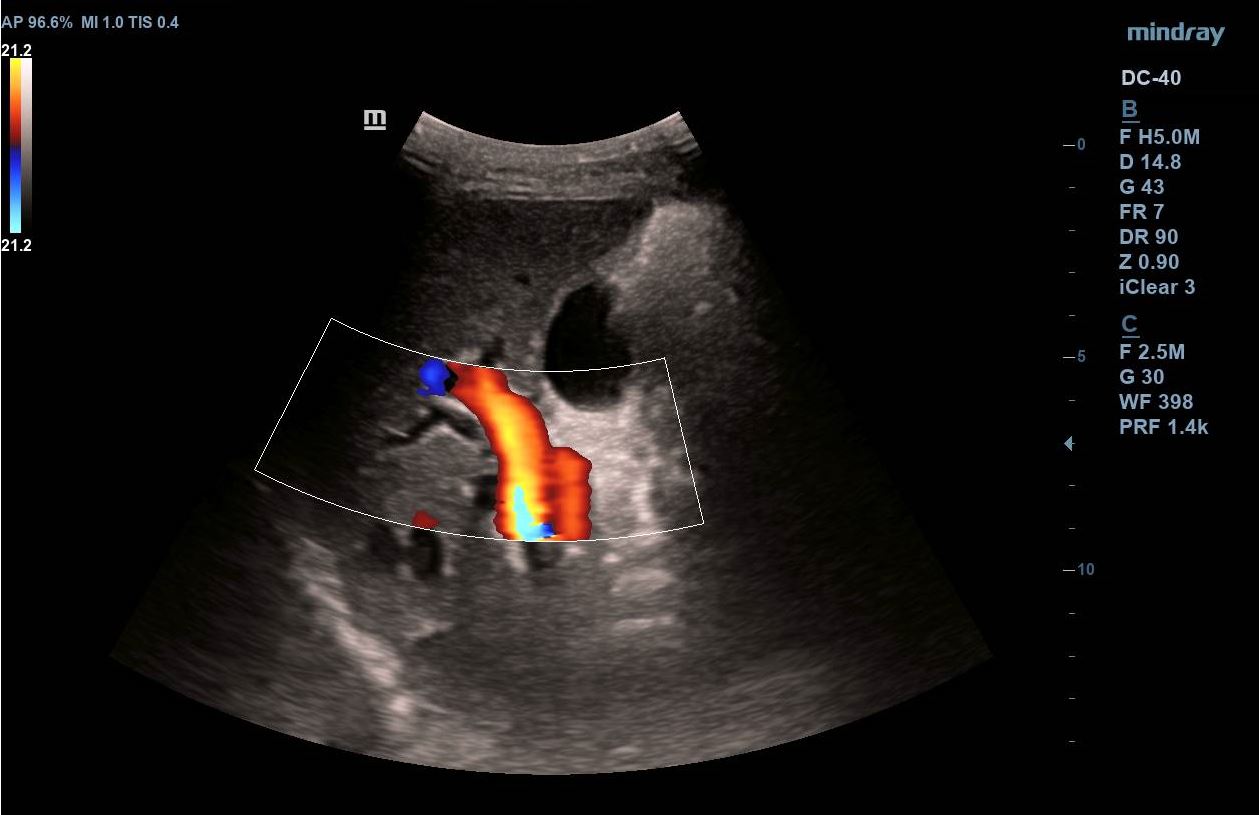

Se realiza ecografía clínica abdominal visualizando en región epigástrica masa de 5,7 x 4,6 cm de aspecto heterogéneo, con un componente principal hipoecogénico y áreas de mayor intensidad. Presenta mapa color positivo y dilatación de colédoco.

Se inicia estudio, confirmando en ecografía abdominal reglada la presencia de una masa sólida en cabeza-cuello pancreático de 5 x 4 cm con dilatación de la vía biliar intra y extrahepática y en TAC toraco-abdomino-pélvico masa hipervascular en cabeza y cuerpo pancreático con áreas de degeneración quística, dilatación del árbol biliar y atrofia del páncreas distal. Posteriormente, se realiza una ecoendoscopia en la que se informa de una masa pancreática con engrosamiento de la papila duodenal, así como dilatación de la vía biliar extrahepática.